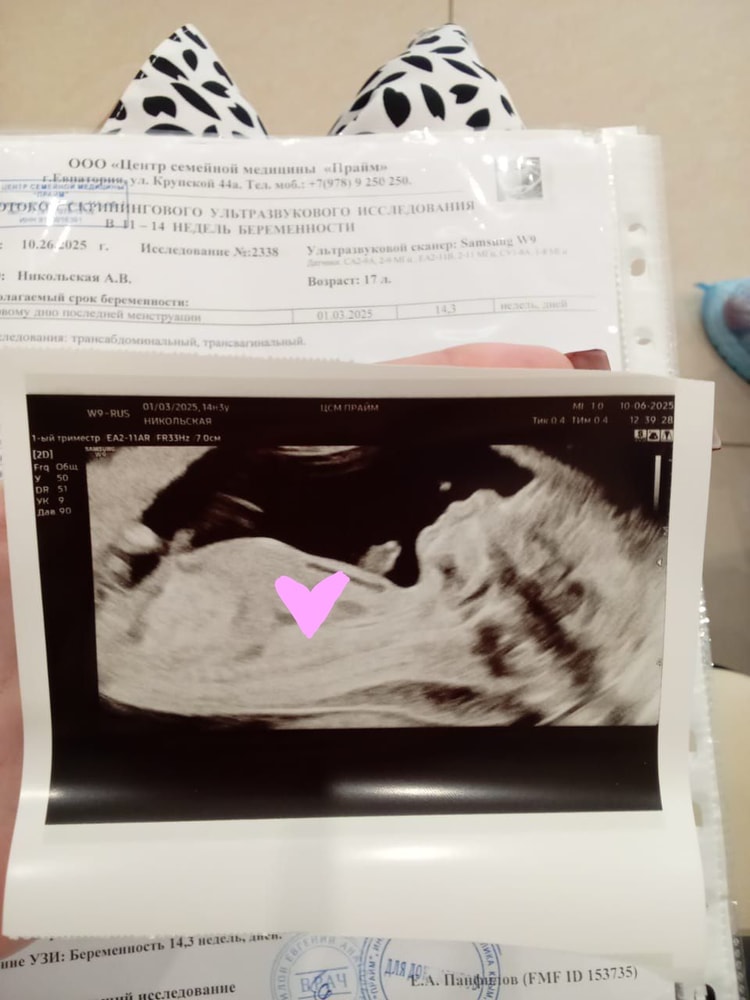

Страхи, переживания и немножечко нытьяНачнем с моей непростой истории беременности, которая продолжается по сей день и доказывает, что до последнего нужно верить и бороться, даже когда результаты говорят об обратном. Уже в 11 недель в клинике врач заметила пупочную грыжу и расширение твп, но не написала сколько, только в общих чертах, конечно запугали и я расплакалась при молодом человеке на узи, весь день как на иголках и разные мысли, что у меня может быть больной ребенок. На первом скрининге 12нед+5, большое расширение твп опять, 8.6мм(очень много), а так все в норме и патологий не выявлено, даже носовая кость, я так же плакала и не знала чего ждать и готовиться ли.. Повторное узи в 14+3 недели и твп уже 5-6мм, все органы и строение так же в норме, плохие анализы из женской консультации, опять слезы и риск Дауна 1:4, Эдвардса 1:23, я хотела провалиться сквозь землю, но надежда была на биопсию хориона, которую я поехала делать 17 июня в 15+3 недели, сама процедура была болезненная и я долго отходила от прокола, так же мучала тошнота (адский токсикоз который иногда и сейчас проявляется) после этого я поехала домой на такси 2 часа в дороге и нервы в ожидании результатов, страхи про последствия процедуры. Вот он долгожданный результат, мальчик, 46 хромосом, нормальный ребенок, моему счастью нет предела и теперь я верю во все и всех девушек, женщин, находящихся в похожей ситуации как я, хочу успокоить и сказать что не все потеряно! Даже если все врачи говорят что все ужасно и никто не верит в чудо, нужно стоять на своем и пройти сложный путь, для наступления светлой полосы в жизни, надеюсь моя история была интересна и полезна для вас😌❤